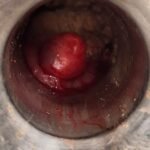

LASER LIAS FOR ANAL FISSURES AND BANDING OF HEMORRHOIDS